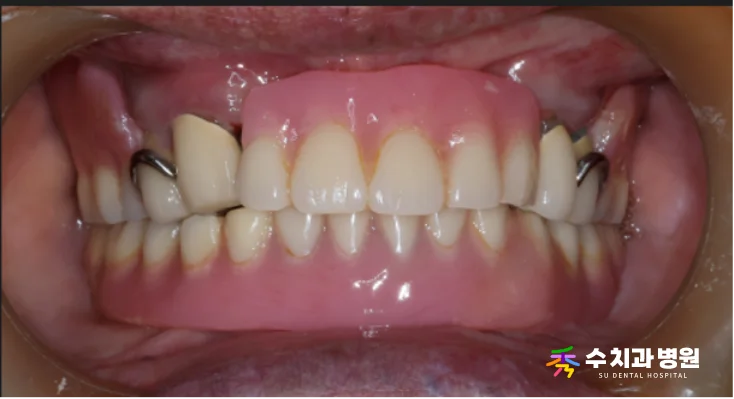

🔍 치료 전

기존에 사용하시던 부분틀니를 지지하던

남은 치아들이 지속적인 자극과 압력을 받으면서,

심하게 흔들리고 주변 잇몸뼈의 흡수가

상당히 진행된 상태였습니다.

[📸 치료 전 사진] (촬영일: 2025년 4월)